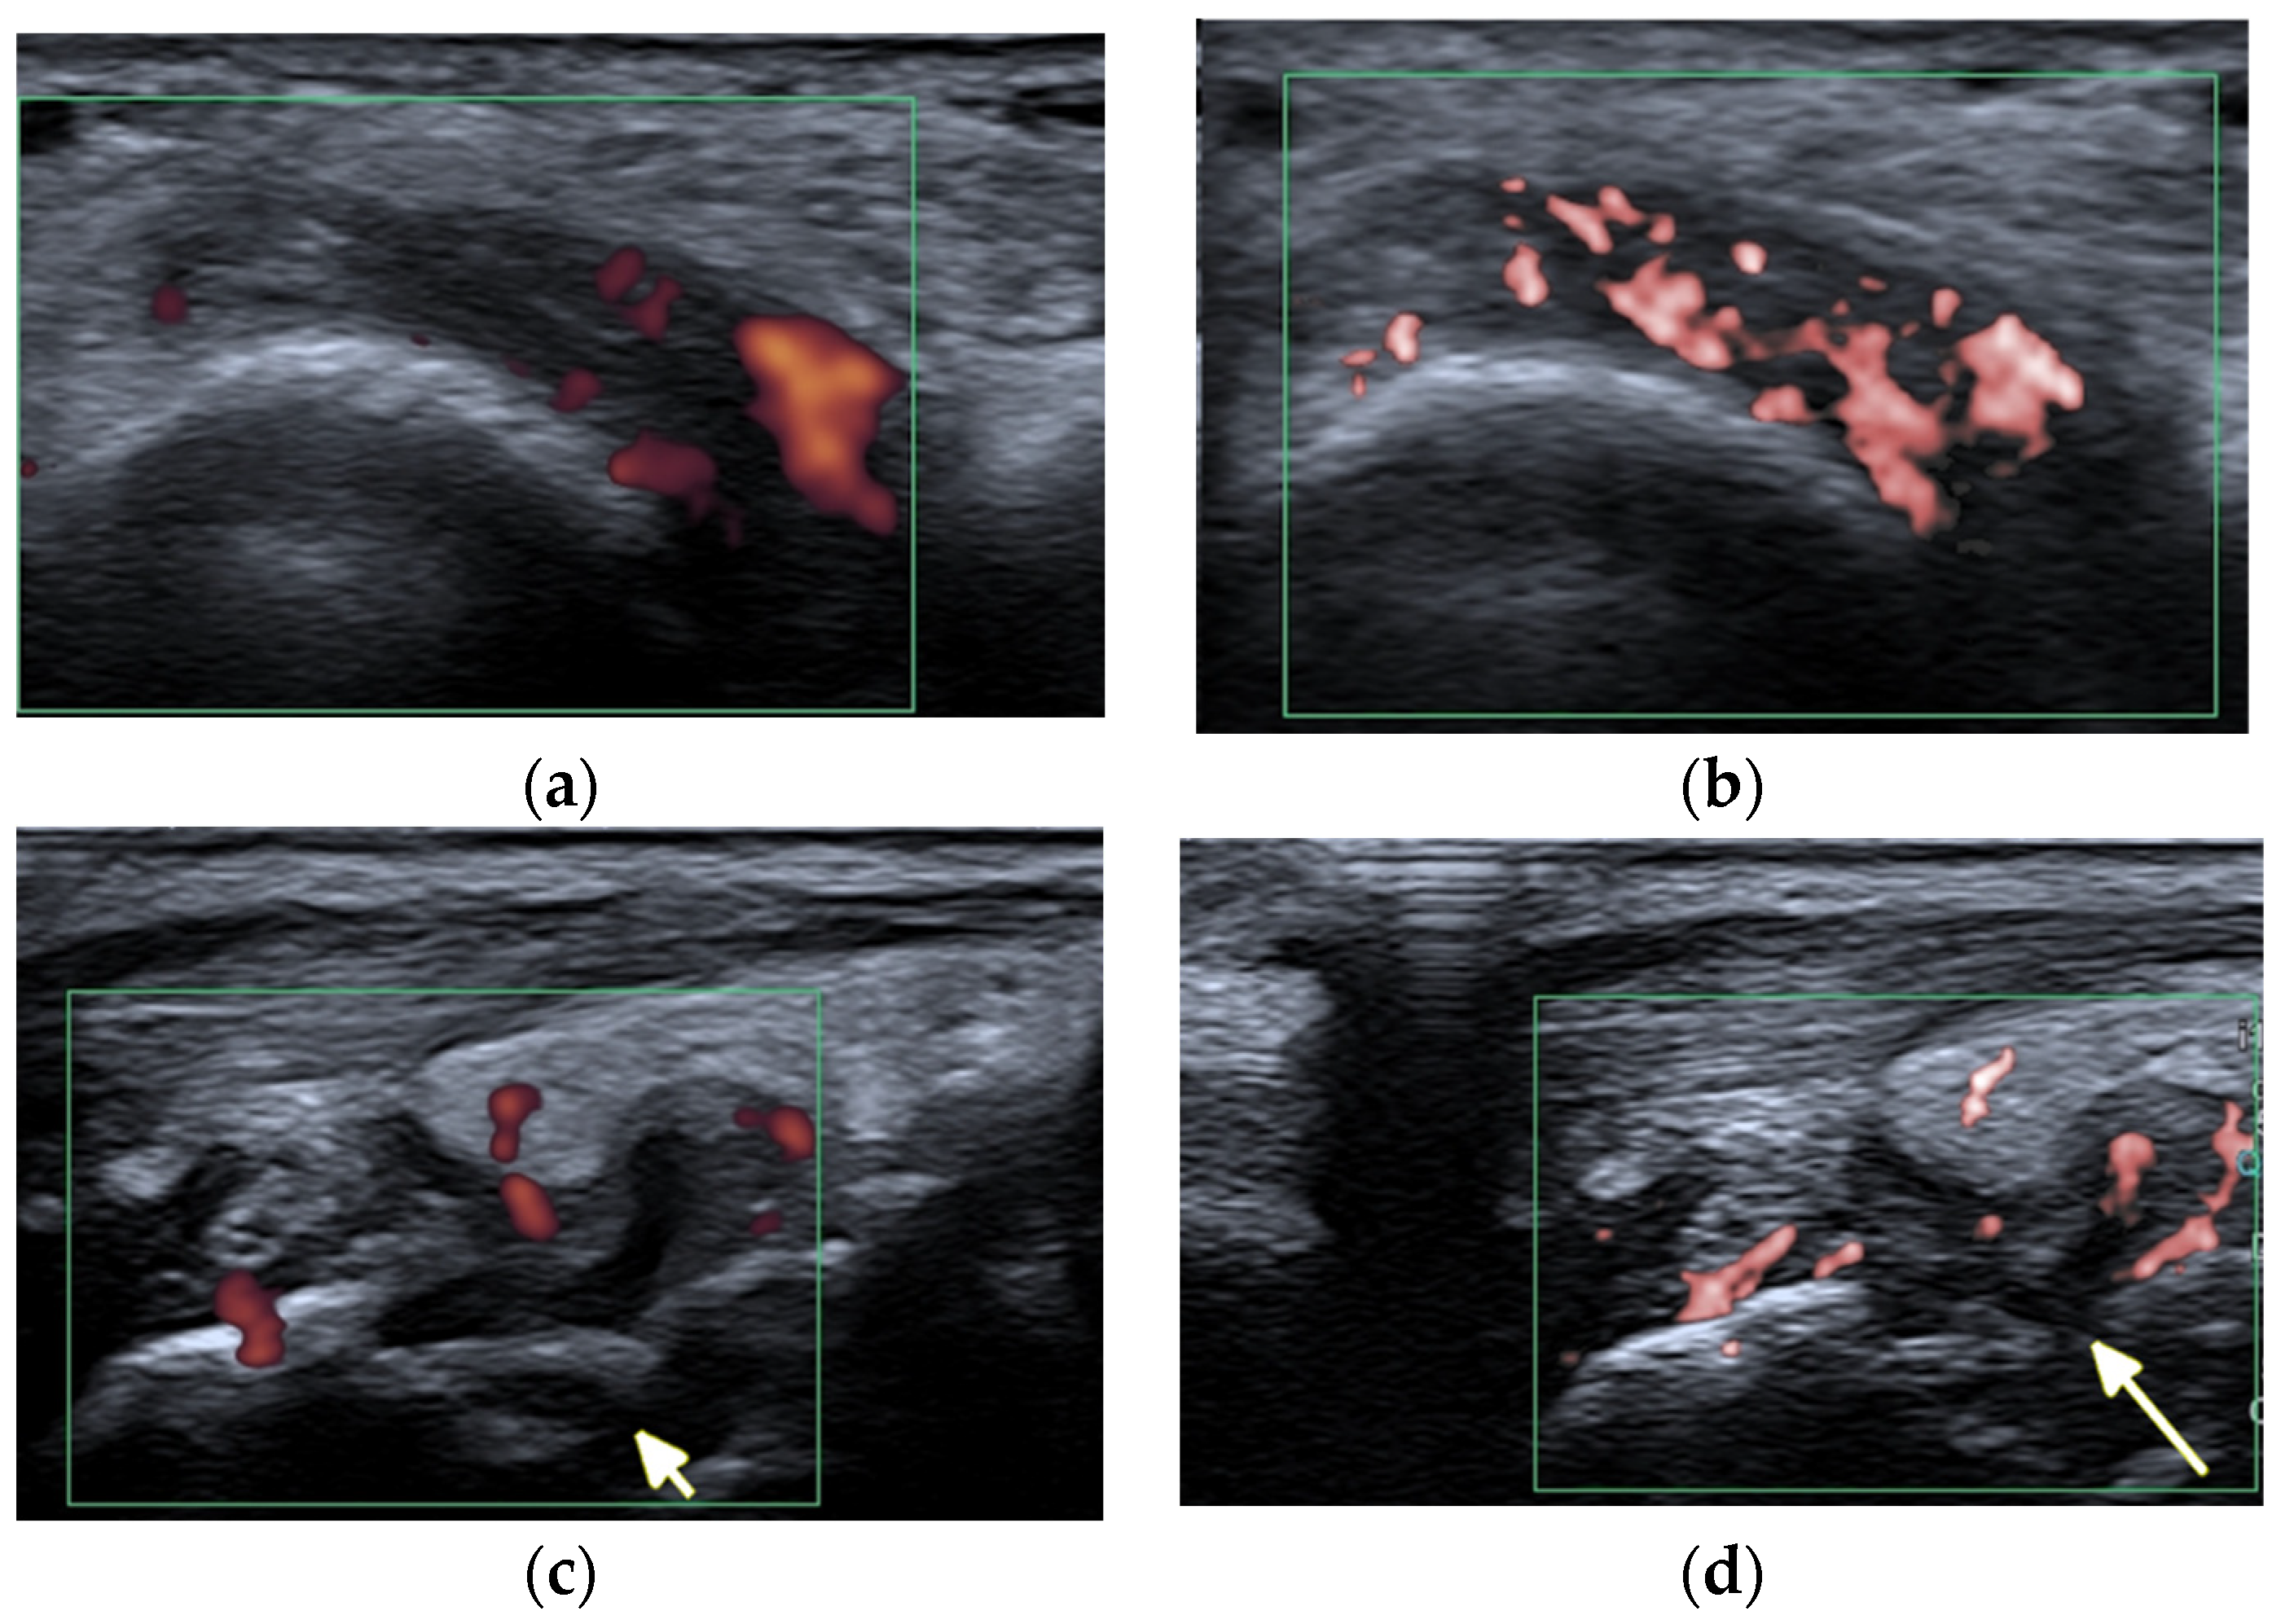

Ultrasound (US) and MRI show effusions and synovial and/or tenosynovial hypertrophy. Power and color doppler US, including newer microvascular techniques and contrast-enhanced MRI, show active synovial inflammation [2] (Figure 1). Compared with RA, the swelling caused by effusion and synovial hyperplasia and vascularity in SLE arthritis is relatively light [2]. Pathology reveals widespread vasculitis affecting capillaries, arterioles, and venules, and—unlike pannus in RA—villous hypertrophy of the synovium covered by fibrin and low-grade lymphoplasmacytic inflammatory cell infiltrates in the subintima [5].

Figure 1.

A 34-year-old female with systemic lupus erythematosus. (a) Posterior–anterior and oblique (b) radiographs of the bilateral hands show a non-united fracture of the right scaphoid waist, with increased sclerosis of the proximal pole and proximal waist consistent with osteonecrosis (arrow), possibly steroid-induced, and with no additional deformities. (c) Long-axis power Doppler ultrasound images at the volar aspect of the ring finger, (d) dorsal ulnar aspect of the wrist, and (e) volar aspect of the wrist show increased synovial vascularity involving the ring finger in (c) and the 6th extensor compartment tendon sheath in (d), consistent with tenosynovitis (arrows). Synovitis at the volar aspect of the radiocarpal and midcarpal joints without erosive bone changes is seen in (e) (arrowheads).